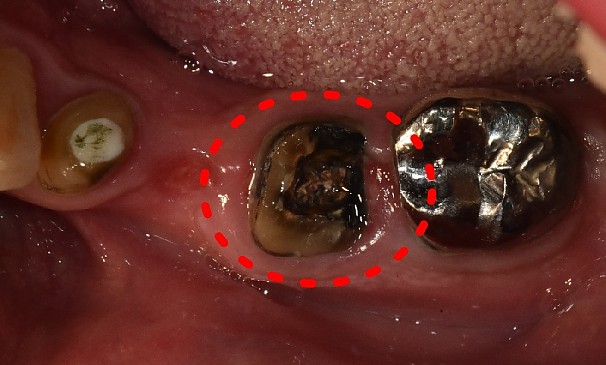

치아머리 확보술란?

선천적으로 치관(치아머리)이 짧거나, 사고로 치관의 일 부분이 깨졌을 경우,

크라운을 씌울 때 남아 있는 치관의 길이가 부족해서 크라운이 탈락할 가능성이 클 때 크라운의 길이를 확보하기 위해

잇몸 부분을 절개하여 치아 머리 부분의 길이를 확보합니다.

치아머리확보술

김OO님 전후사진 | 치료 기간 : 3주

치료 전